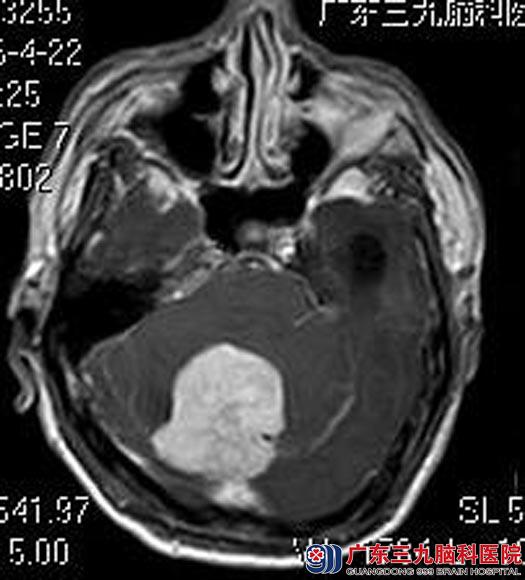

广东三九脑科医院进一步头颅MR检查提示:后颅窝小脑幕右侧幕下脑外占位性病变,大小约为4.1cm×4.7cm×4.2cm,考虑为脑膜瘤;并幕上梗阻性脑积水及小脑扁桃体下疝形成;头颅CTA提示:后颅窝右侧幕下占位性病变血管丰富。